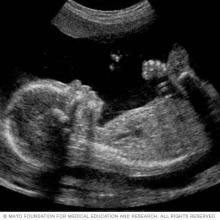

A fetal ultrasound slide showing baby's profile

A 2D fetal ultrasound can help your healthcare professional evaluate your baby's growth and development.

A congenital heart defect may be diagnosed during pregnancy or after birth. Signs of certain heart defects can be seen on a routine pregnancy ultrasound test (fetal ultrasound).